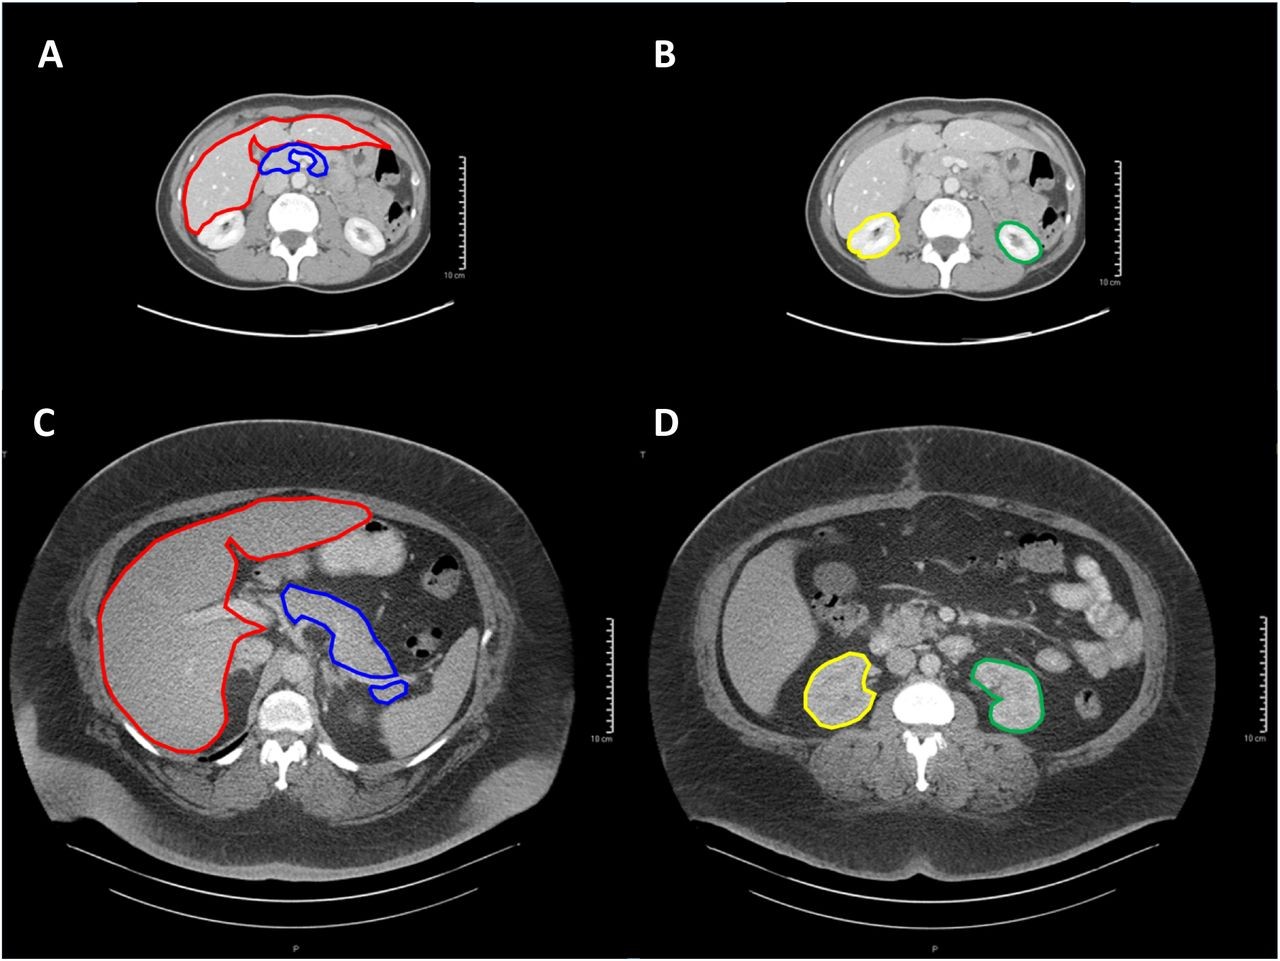

Ученые из США и Франции под руководством Кристиана Томасетти (Cristian Tomasetti) из Университета Джона Хопкинса предположили, что риск развития рака увеличивается при ожирении не из-за изменений в отдельных клетках, а по статистическим причинам. По версии исследователей, у людей с избыточным весом размер органов и число клеток в них больше, а значит, выше шанс появления мутаций.